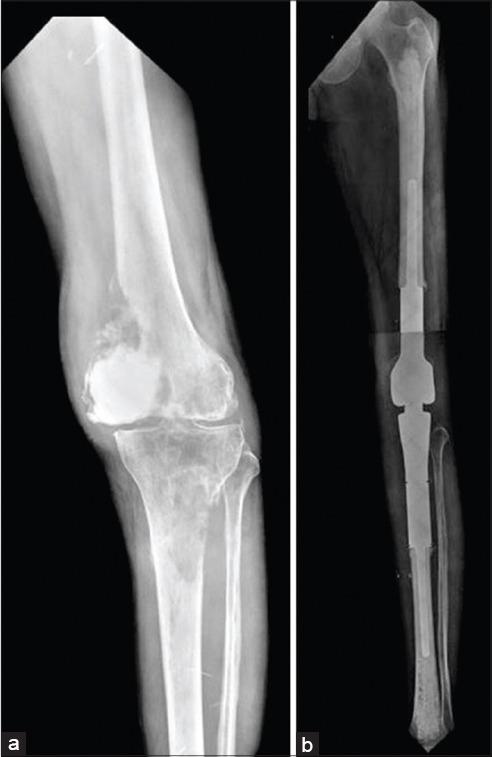

Skeletal metastasis is a common cause of severe morbidity, reduction in quality of life (QOL) and often early mortality. Its prevalence is rising due to a higher rate of diagnosis, better systemic treatment, longer lives with the disease and higher disease burden rate. As people with cancer live longer and with rising sensitivity of body imaging and surveillance, the incidence of pathological fracture, metastatic epidural cord compression is rising and constitutes a challenge for the orthopedic surgeon to maintain their QOL. Metastatic disease is no longer a death sentence condemning patients to "terminal care." In the era of multidisciplinary care and effective systemic targeted and nontargeted therapy, patient expectations of QOL, even during palliative end of care period is high. We lay emphasis on proving the diagnosis of metastasis by biopsy and histopathology and discuss imaging modalities to help estimate fracture risk and map disease extent. This article discusses at length the evidence and decision-making process of various modalities to treat skeletal metastasis. The modalities range from radiation including image-guided, stereotactic and whole body radiation, systemic targeted or hormonal therapy, spinal decompression with or without stabilization, extended curettage with stabilization, resection in select cases with megaprosthetic or biological reconstruction, percutaneous procedures using radio frequency ablation, cementoplasties and discusses the role of emerging modalities like high frequency ultrasound-guided ablation, cryotherapy and whole body radionuclide therapy. The focus lies on the role of multidisciplinary care, which considers complex decisions on patient centric prognosis, comorbidities, cost, feasibility and expectations in order to maximize outcomes on QOL issues.

骨转移是导致严重发病、生活质量(QOL)下降以及常出现早期死亡的常见原因。由于诊断率提高、全身治疗效果更好、患者带病生存时间延长以及疾病负担率上升,其患病率正在上升。随着癌症患者生存期延长以及身体成像和监测的敏感性提高,病理性骨折、转移性硬膜外脊髓压迫的发生率正在上升,这对骨科医生维持患者的生活质量构成了挑战。转移性疾病不再是宣判患者“临终关怀”的死刑判决。在多学科护理以及有效的全身靶向和非靶向治疗时代,即使在姑息性临终关怀阶段,患者对生活质量的期望也很高。我们强调通过活检和组织病理学来证实转移瘤的诊断,并讨论有助于评估骨折风险和描绘疾病范围的成像方式。本文详细讨论了治疗骨转移的各种方式的证据和决策过程。这些方式包括放疗,如影像引导放疗、立体定向放疗和全身放疗、全身靶向或激素治疗、有或无内固定的脊柱减压、扩大刮除术加内固定、在某些病例中进行假体或生物重建的切除术、使用射频消融、骨水泥成形术的经皮手术,并讨论了高频超声引导消融、冷冻疗法和全身放射性核素治疗等新兴方式的作用。重点在于多学科护理的作用,它考虑以患者为中心的预后、合并症、成本、可行性和期望等复杂决策,以最大限度地提高生活质量相关问题的治疗效果。